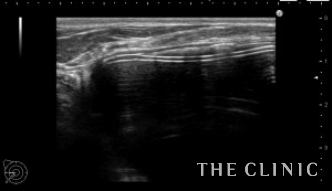

エコーでは一部被膜(カプセル)の石灰化も認めました。

シリコンバッグによるカプセル拘縮のエコー診断カルテ